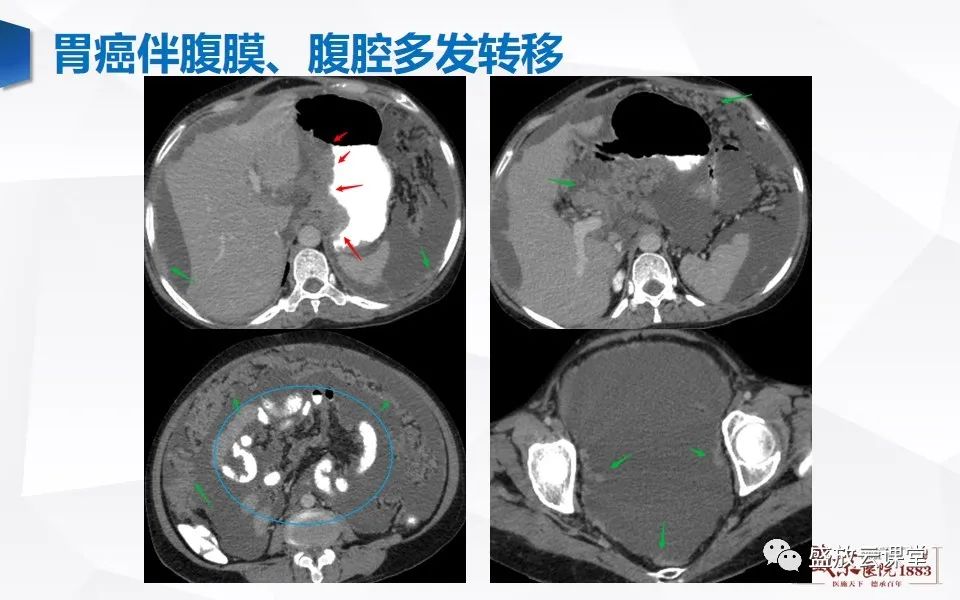

肠系膜解剖及常见病变